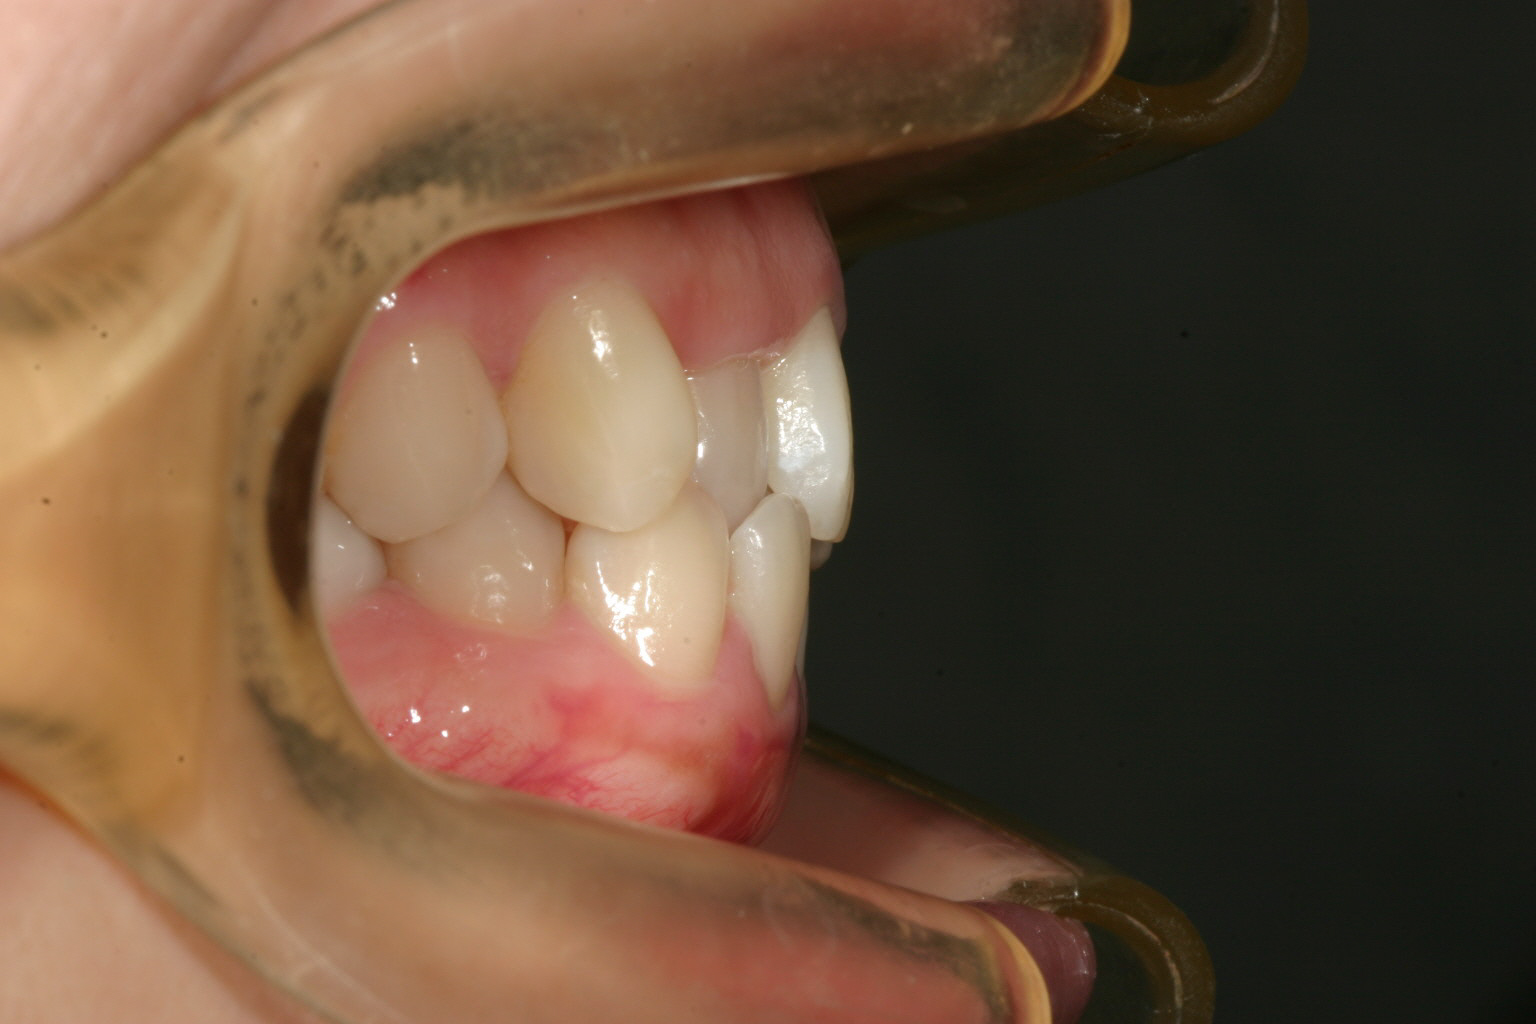

側面観はなんら問題無いです。

側面観は問題無いです。